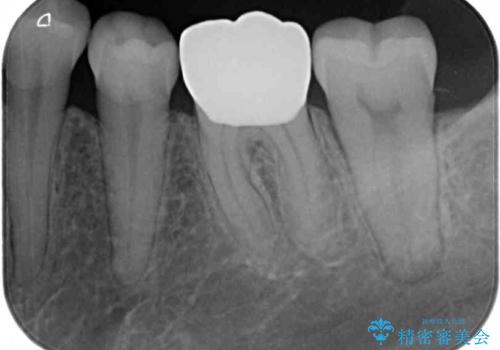

- 人と話す際に、下顎の奥にある銀歯が目立って気になるとのことで来院された患者様です。

左右の奥歯に銀歯のクラウンが装着されていたため、銀歯除去後に仮歯に置き換え、フルジルコニアクラウンにて補綴治療を行うこととしました。